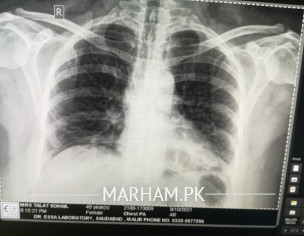

Asking For Someone else, Mother, Female, 50 Years old, karachi

Please examine the x ray and guide is this ok xray is attached. NOTE: She had viral few days back resulting in serious cough and diagnosed with chest infection…. This xray is taken after recovery

comparison with previous x-ray required

yes chest infection